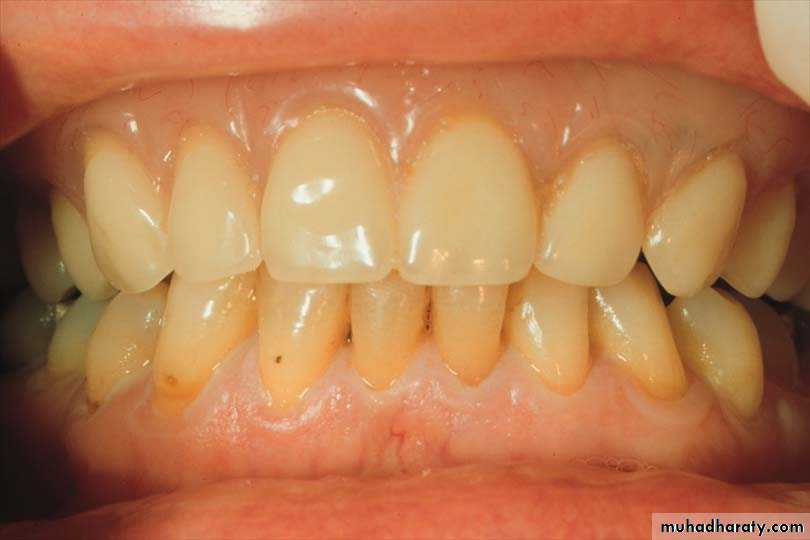

1. Conventional Immediate Denture (CID): A complete or removable partial denture or overdenture fabricated for placement immediately after the removal of natural teeth. The posterior teeth would be extracted and allowed to heal before the anterior teeth extraction The denture is intended to be relined to serve as the long—term prosthesis.

2. Interim Immediate Denture (IID):All remaining teeth are extracted on that day and immediate denture inserted on same day. After healing is completed ,second new denture is fabricated and inserted as long term prosthesis